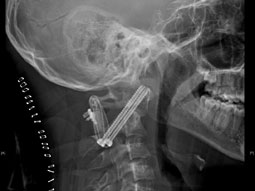

تمكن فريق طبي بمدينة الملك فهد الطبية من إجراء عملية معقدة لمريض سعودي، لإعادة كسر وخلع بليغ للفقرة العنقية الأولى والثانية تحت قاع الجمجمة، باستخدام تقنية تثبيت الفقرة العنقية الأولى مع الثانية عن طريق مسمارين من خلال المفصلين مع التثبيت الخلفي، وتُعد هذه العملية من العمليات المعقدة والنادرة نظراً لمرور المسمارين بين الحبل الشوكي من جهة والشريان الفقاري من جهة أخرى باتجاه قاع الجمجمة.وقال الدكتور إبراهيم عسيري استشاري جراحة العظام والمفاصل والعمود الفقري، رئيس الفريق الطبي إن المريض تعرض لحادث سير تسبب في إصابات بليغة بالدماغ وكسور متفرقة في الأطراف اليمنى، أُدخل على إثرها العناية المركزة في أحد المستشفيات، مشيراً إلى أنه لم يتم معالجة الكسر الموجود في النتوء السني في الفقرة العنقية الثانية مع وجود خلع دوراني بين الفقرة العنقية الأولى والثانية تحت الجمجمة، ووضع له مثبت خارجي للعنق. وأفاد عسيري أنه تم استقبال الحالة في مدينة الملك فهد الطبية وأجريت له الفحوصات الطبية اللازمة وتم تشكيل فريق طبي لهذه الحالة وبعد بحث كافة الخيارات الطبية والمضاعفات المحتملة لكل خيار تم اطلاع المريض وذويه على هذه الخيارات، وكان الخيار الأمثل إجراء العملية لأن ترك المريض بدون عملية قد يؤدي إلى الوفاة أو الشلل الكامل في حالة حدوث أي إصابة بسيطة أخرى أو سقوط على المنطقة المصابة.

وزاد عسيري: بدأنا التحضير للعملية حيث وضع المريض في شد للجمجمة وذلك لتسهيل عملية إعادة الخلع مع الكسر إلى وضعهما الطبيعي خصوصاً أنه مرَّ على الإصابة أكثر من ثمانية أشهر مما تسبب في وجود بعض التكلسات والتليفات في تلك المنطقة التي تحتاج لتفكيك باستخدام الشد الرأسي، مع وجود ضغط على الحبل الشوكي وقلة المساحة المتاحة له، وكذلك وجود شد على الشريان الفقاري المغذي للدماغ. وذكر عسيري أن الفريق الطبي عمد إلى فتح المنطقة من خلف العنق وتمت إعادة الكسر والخلع لوضعه الطبيعي من دون حدوث أي مضاعفات، مؤكداً أن هامش الخطأ في هذه العملية لا يتجاوز 1 - 2 مليمتر، باستخدام جهاز الأشعة السينية الجراحية فقط والعلامات التشريحية، وهذه التقنية تركز على المنطقة المصابة فقط، وتجنب المريض تثبيت الجمجمة مع الفقرات العنقية، وبالتالي تحافظ على جزء كبير من الحركة بينهما.

وأضاف عسيري: بدت الفقرتان في وضعهما الطبيعي بعد التثبيت، وتمت إزالة الضغط عن الحبل الشوكي بدون إزالة الجزء الخلفي لكلا الفقرتين، ولم تحدث أي مضاعفات للمريض بعد العملية ولله الحمد، مبيناً أن المريض غادر المستشفى بعد فترة وجيزة من إجراء العملية وأنه يستطيع المشي باستخدام مثبت خارجي مؤقت لحين التئام العملية.